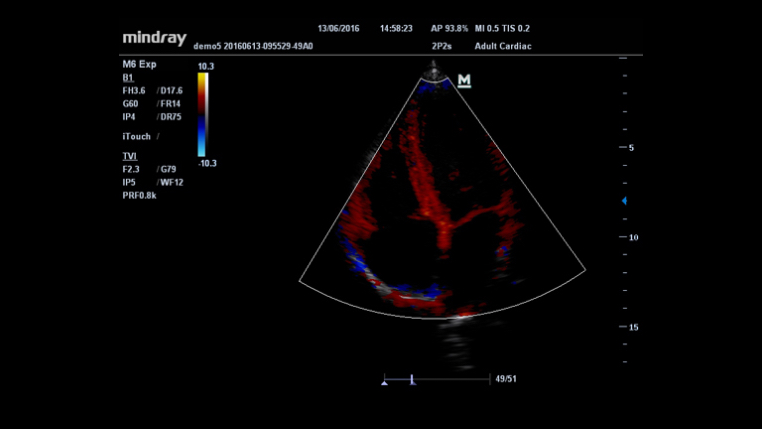

UWN ?? ??(???? ???)

UWN ?? ??? ?? M6? 2? ??? ? ??? ?? ??? ?? ???? ???? ?? ??? ??? ??? ? ????.

- ?? ??? ??? ??, ??? ??? ???

- ?? MI ??? ?? ??? ?? ?? ??